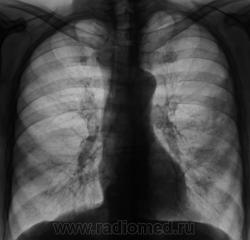

Пол пациента: Мужской пол Тип патологии: Инфекция Область исследования: Грудная клетка и верхние дыхательные пути Методы исследования: Rg Пациент направлен в рентгеновский кабинет терапевтом Для рентгенографии ОГК с подозрением на левостороннюю пневмонию. Произведено стандартное исследование. https://radiomed.ru/sites/default/files/styles/case_slider_image/public/user/12/02_Dinamika..JPG?itok=d6uk1vVu ID:2510 Sat, 03/04/2010 - 01:50 #1 Петрович Offline Last seen: 7 years 5 months ago Joined: 22.03.2009 - 01:13 Posts: 3908 Небольшой интенсивности воспаление в S4 исключить трудно. Но видимые на картинках изменения преимущественно плеврокостальные. Неоднозначно всё Sat, 03/04/2010 - 08:16 #2 Игорь Иванович Offline Last seen: 3 years 12 months ago Joined: 23.01.2010 - 14:56 Posts: 3695 За что боролись, на то и напоролись. Хотели - получите. А на контроле посмотрим. Sat, 03/04/2010 - 09:09 #3 Катенёв Валенти... Offline Last seen: 7 years 3 months ago Joined: 22.03.2008 - 22:15 Posts: 54876 Игорь Иванович wrote: За что боролись, на то и напоролись. Хотели - получите. А на контроле посмотрим. Конечно "ПОСМОТРИМ", и скоро, но не разъвеет "контроль" ничего, так как "лечение" бывает всякое... Sat, 03/04/2010 - 10:19 #4 Катенёв Валенти... Offline Last seen: 7 years 3 months ago Joined: 22.03.2008 - 22:15 Posts: 54876 "Динамика". Через 10 дней после противовоспалительного лечения. Может лечили не так как надо? Приложения: Sat, 03/04/2010 - 11:09 #5 Грицько Виталий Offline Last seen: 9 years 2 months ago Joined: 05.01.2010 - 14:06 Posts: 1058 Дауж динамика не слабая... Sat, 03/04/2010 - 12:07 #6 Петрович Offline Last seen: 7 years 5 months ago Joined: 22.03.2009 - 01:13 Posts: 3908 Катенёв Валентин Львович wrote: Игорь Иванович wrote: За что боролись, на то и напоролись. Хотели - получите. А на контроле посмотрим.Конечно "ПОСМОТРИМ", и скоро, но не разъвеет "контроль" ничего, так как "лечение" бывает всякое... Вы о чём, панове? Что я пропустил? Дайте ссылку что ли.. Неоднозначно всё Sat, 03/04/2010 - 12:13 #7 Петрович Offline Last seen: 7 years 5 months ago Joined: 22.03.2009 - 01:13 Posts: 3908 Тут наверное, без анализа пунктата не разобраться.. Неоднозначно всё Sat, 03/04/2010 - 13:48 #8 Катенёв Валенти... Offline Last seen: 7 years 3 months ago Joined: 22.03.2008 - 22:15 Posts: 54876 Петрович wrote: Тут наверное, без анализа пунктата не разобраться.. Или анализа "лечения" (таблетированного) в домашних условиях. Sat, 03/04/2010 - 14:06 #9 Катенёв Валенти... Offline Last seen: 7 years 3 months ago Joined: 22.03.2008 - 22:15 Posts: 54876 Конечно были произведены томограммы в прямой проекции. Приложения: Sat, 03/04/2010 - 14:09 #10 Катенёв Валенти... Offline Last seen: 7 years 3 months ago Joined: 22.03.2008 - 22:15 Posts: 54876 Конечно, ьыли произведены и томограммы в боковой проекции. Приложения: Sat, 03/04/2010 - 14:30 #11 Петрович Offline Last seen: 7 years 5 months ago Joined: 22.03.2009 - 01:13 Posts: 3908 Хотелось бы получше увидеть бронхиальное дерево. Ведь не для выпота, наверное, томограммы делались? Неоднозначно всё Sat, 03/04/2010 - 14:44 #12 Грицько Виталий Offline Last seen: 9 years 2 months ago Joined: 05.01.2010 - 14:06 Posts: 1058 Петрович wrote: Хотелось бы получше увидеть бронхиальное дерево. Ведь не для выпота, наверное, томограммы делались? Выпот зальет, достоверно без его откачки не получится. Sat, 03/04/2010 - 14:50 #13 Петрович Offline Last seen: 7 years 5 months ago Joined: 22.03.2009 - 01:13 Posts: 3908 Грицько Виталий wrote: Петрович wrote: Хотелось бы получше увидеть бронхиальное дерево. Ведь не для выпота, наверное, томограммы делались? Выпот зальет, достоверно без его откачки не получится. Бронхи выпот не зальёт, даже не сдавит, сместит их только. Неоднозначно всё Sat, 03/04/2010 - 15:15 #14 Грицько Виталий Offline Last seen: 9 years 2 months ago Joined: 05.01.2010 - 14:06 Posts: 1058 Петрович wrote: Грицько Виталий wrote: Петрович wrote: Хотелось бы получше увидеть бронхиальное дерево. Ведь не для выпота, наверное, томограммы делались? Выпот зальет, достоверно без его откачки не получится. Бронхи выпот не зальёт, даже не сдавит, сместит их только. Затемнение такого выпота на линейке не размазывается, нормальную картинку не получиш. Тем более ловить смещеные бронхи ой как не просто.

Небольшой интенсивности воспаление в S4 исключить трудно. Но видимые на картинках изменения преимущественно плеврокостальные.

"Динамика". Через 10 дней после противовоспалительного лечения.

Может лечили не так как надо?

Дауж динамика не слабая...

Тут наверное, без анализа пунктата не разобраться..